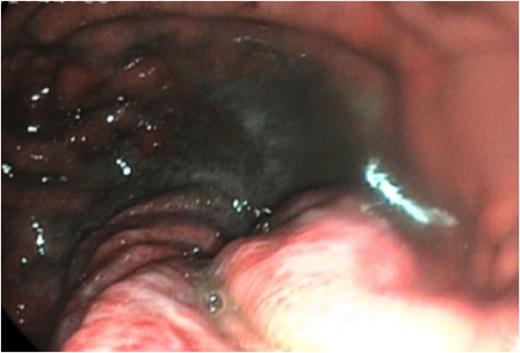

The presumptive diagnosis was of band migration, and an urgent upper G.I. endoscopy was performed. This demonstrated a normal calibre proximal stomach, which narrowed sharply at the mid-body (fig 1.).

OGD showing a normal calibre proximal stomach, which narrowed sharply at the mid-body.